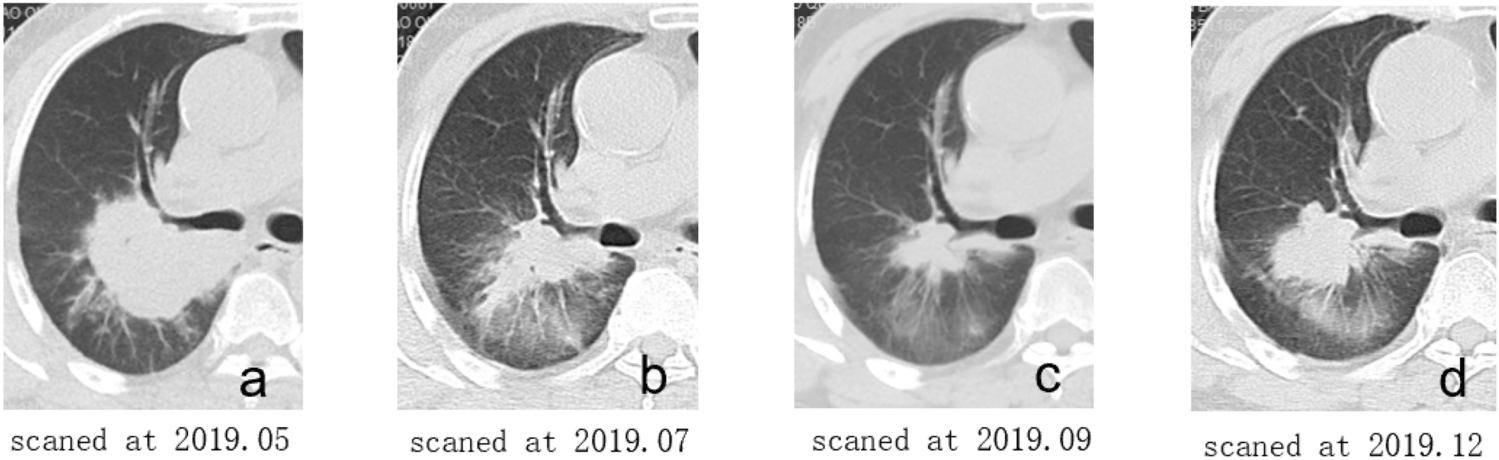

Figure 1

Illustrations of follow-up CT non-enhanced lung images at four different time points. Follow-up CT images of a 66 years old man who underwent EGFR-TKIs therapy because of lung adenocarcinoma with exon 19 deletion mutation. (a) the baseline image before TKIs therapy, included in the baseline images; (b) the first follow-up image after TKIs therapy, included in FFT; (c) the last follow-up image before radiographic advance, included in EAR; (d) the radiographic advance image.